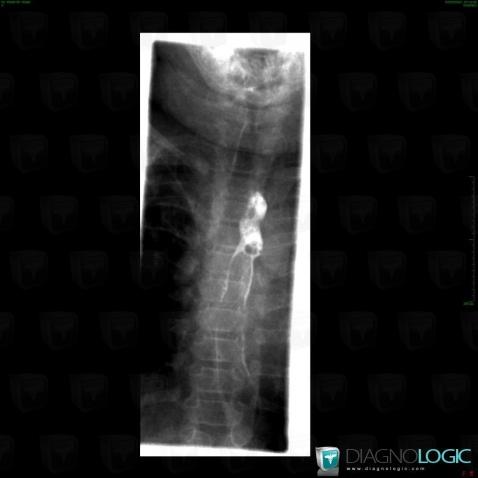

Aberrant right subclavian artery, Oesophagus, X rays

Here is the specific information in the key image above:

- Diagnosis Aberrant right subclavian artery (link to Vascular anomaly), Location(s) Oesophagus, with gamuts Esophageal extrinsic compression

- Diagnosis Aberrant right subclavian artery, Location(s) Supra aortic vessels, with gamuts